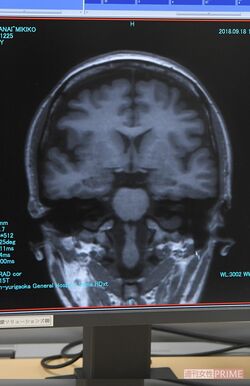

海馬が萎縮すると認知症のリスクが高まる

「MRI画像によって前頭葉、後頭葉に萎縮がないかどうかを見るのと同時に、海馬の萎縮も確認します。記憶をつかさどる海馬が萎縮すると認知症になるリスクが高まるからです。